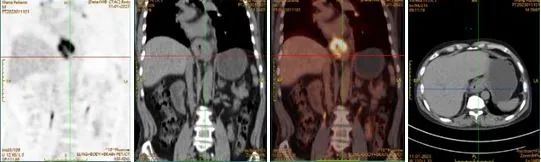

第一次MDT后,结论为因CT提示胸膜左侧斜裂实性小结节,不排除转移瘤可能。建议完善PET-CT了解有无远处转移。这是判断肿瘤分期、手术效果和预后的关键;影像检查提示食管受侵犯较多,建议行食管造影了解受侵范围。由此判断手术难度较大,建议先进行新辅助化疗后再做外科手术,确保手术治疗效果。

PET-CT结果出来后,于泳主任组织了第二次MDT,PET-CT提示食管下段及贲门低分化腺癌伴区域淋巴结转移,病理免疫组化提示Her2阴性,PD-L1(SP263)(肿瘤细胞1%,免疫细胞2%+)。专家们再次建议新辅助化疗后再行外科手术,根据术后病理及免疫组化结果制定术后化疗方案。